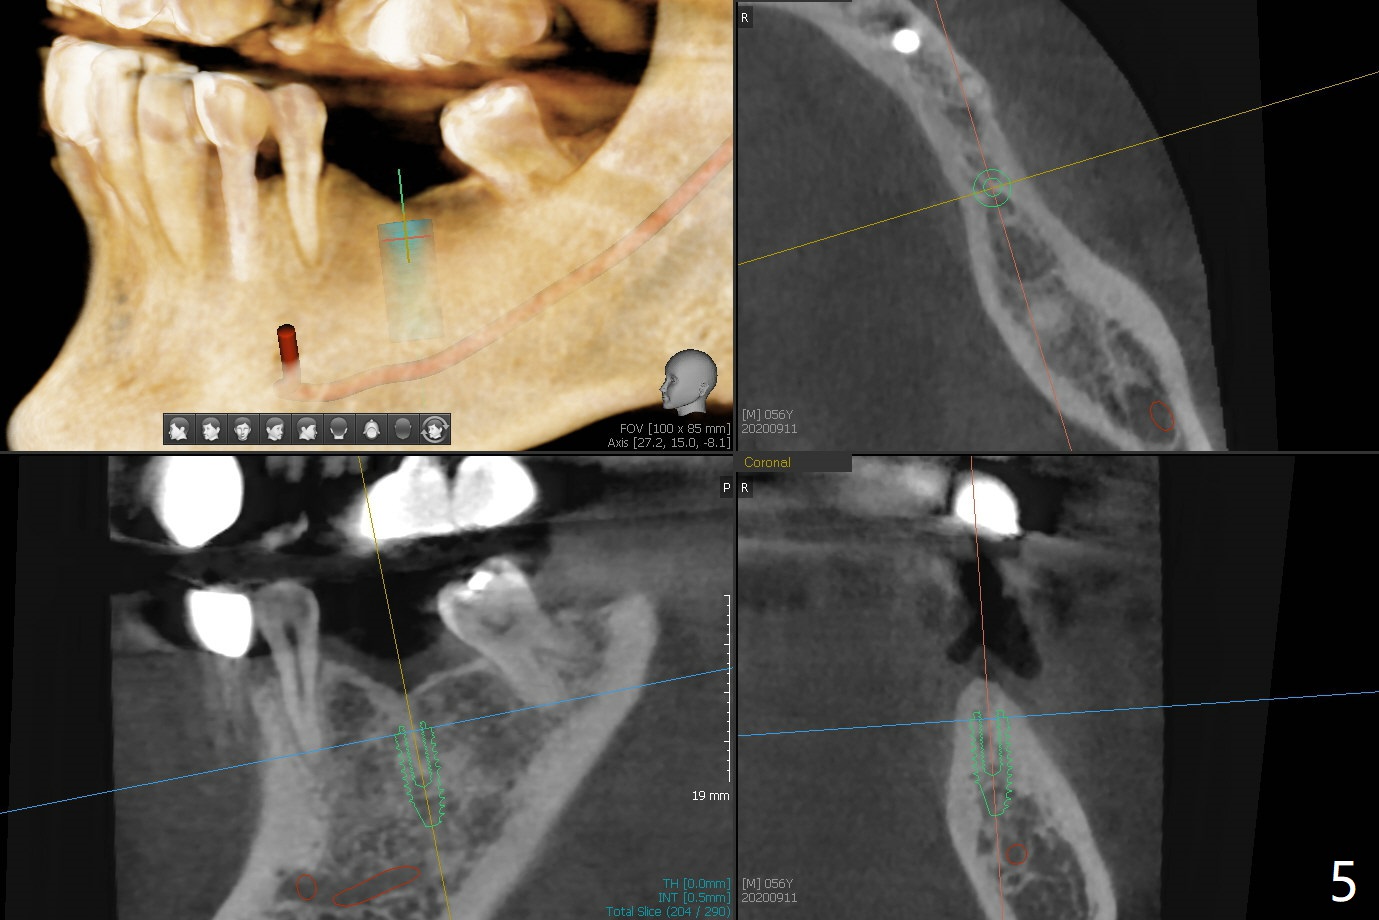

56岁男,高血压,紧张怕痛,要求迅速手术,所以我们初步选择导航。由于他还能在右边咀嚼,先做左侧植牙。左侧好像缺失两个牙齿(图一),不过近远中间隙更象缺失一个牙齿(图二)。牙槽嵴狭窄,骨皮质厚,容易植骨吗?还是容易劈开?牙槽嵴狭窄(图三,四,六)似乎适合种植两个小植体(两个双尖牙)。如果只植入一个,牙槽骨高度差些,植体短(图五),仿佛做牙槽嵴劈开术比较好。